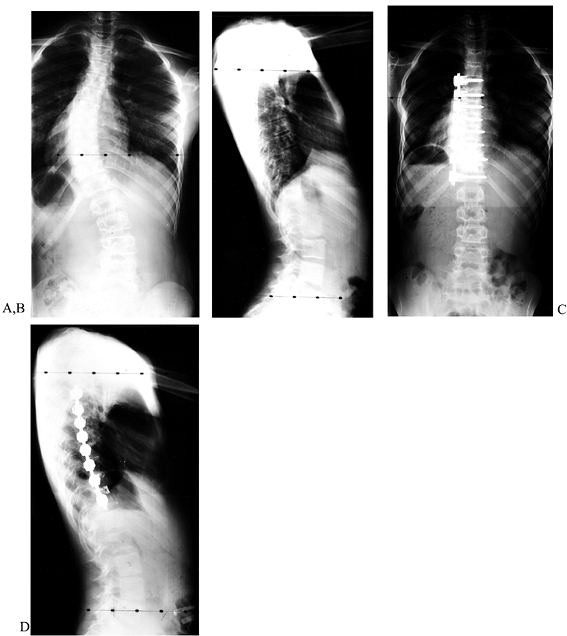

obtained with this instrumentation. Preoperative side-bending films of

a thoracic curve show excellent flexibility. The postoperative

anteroposterior (AP) and lateral films show near-complete correction.

Figure 155.17. The preoperative AP (A) and lateral (B) views of a child with a thoracic scoliosis. The postoperative films (C,D)

show near complete correction of the coronal and sagittal deformities. The cage is used to prevent kyphosis at the thoracolumbar junction. |